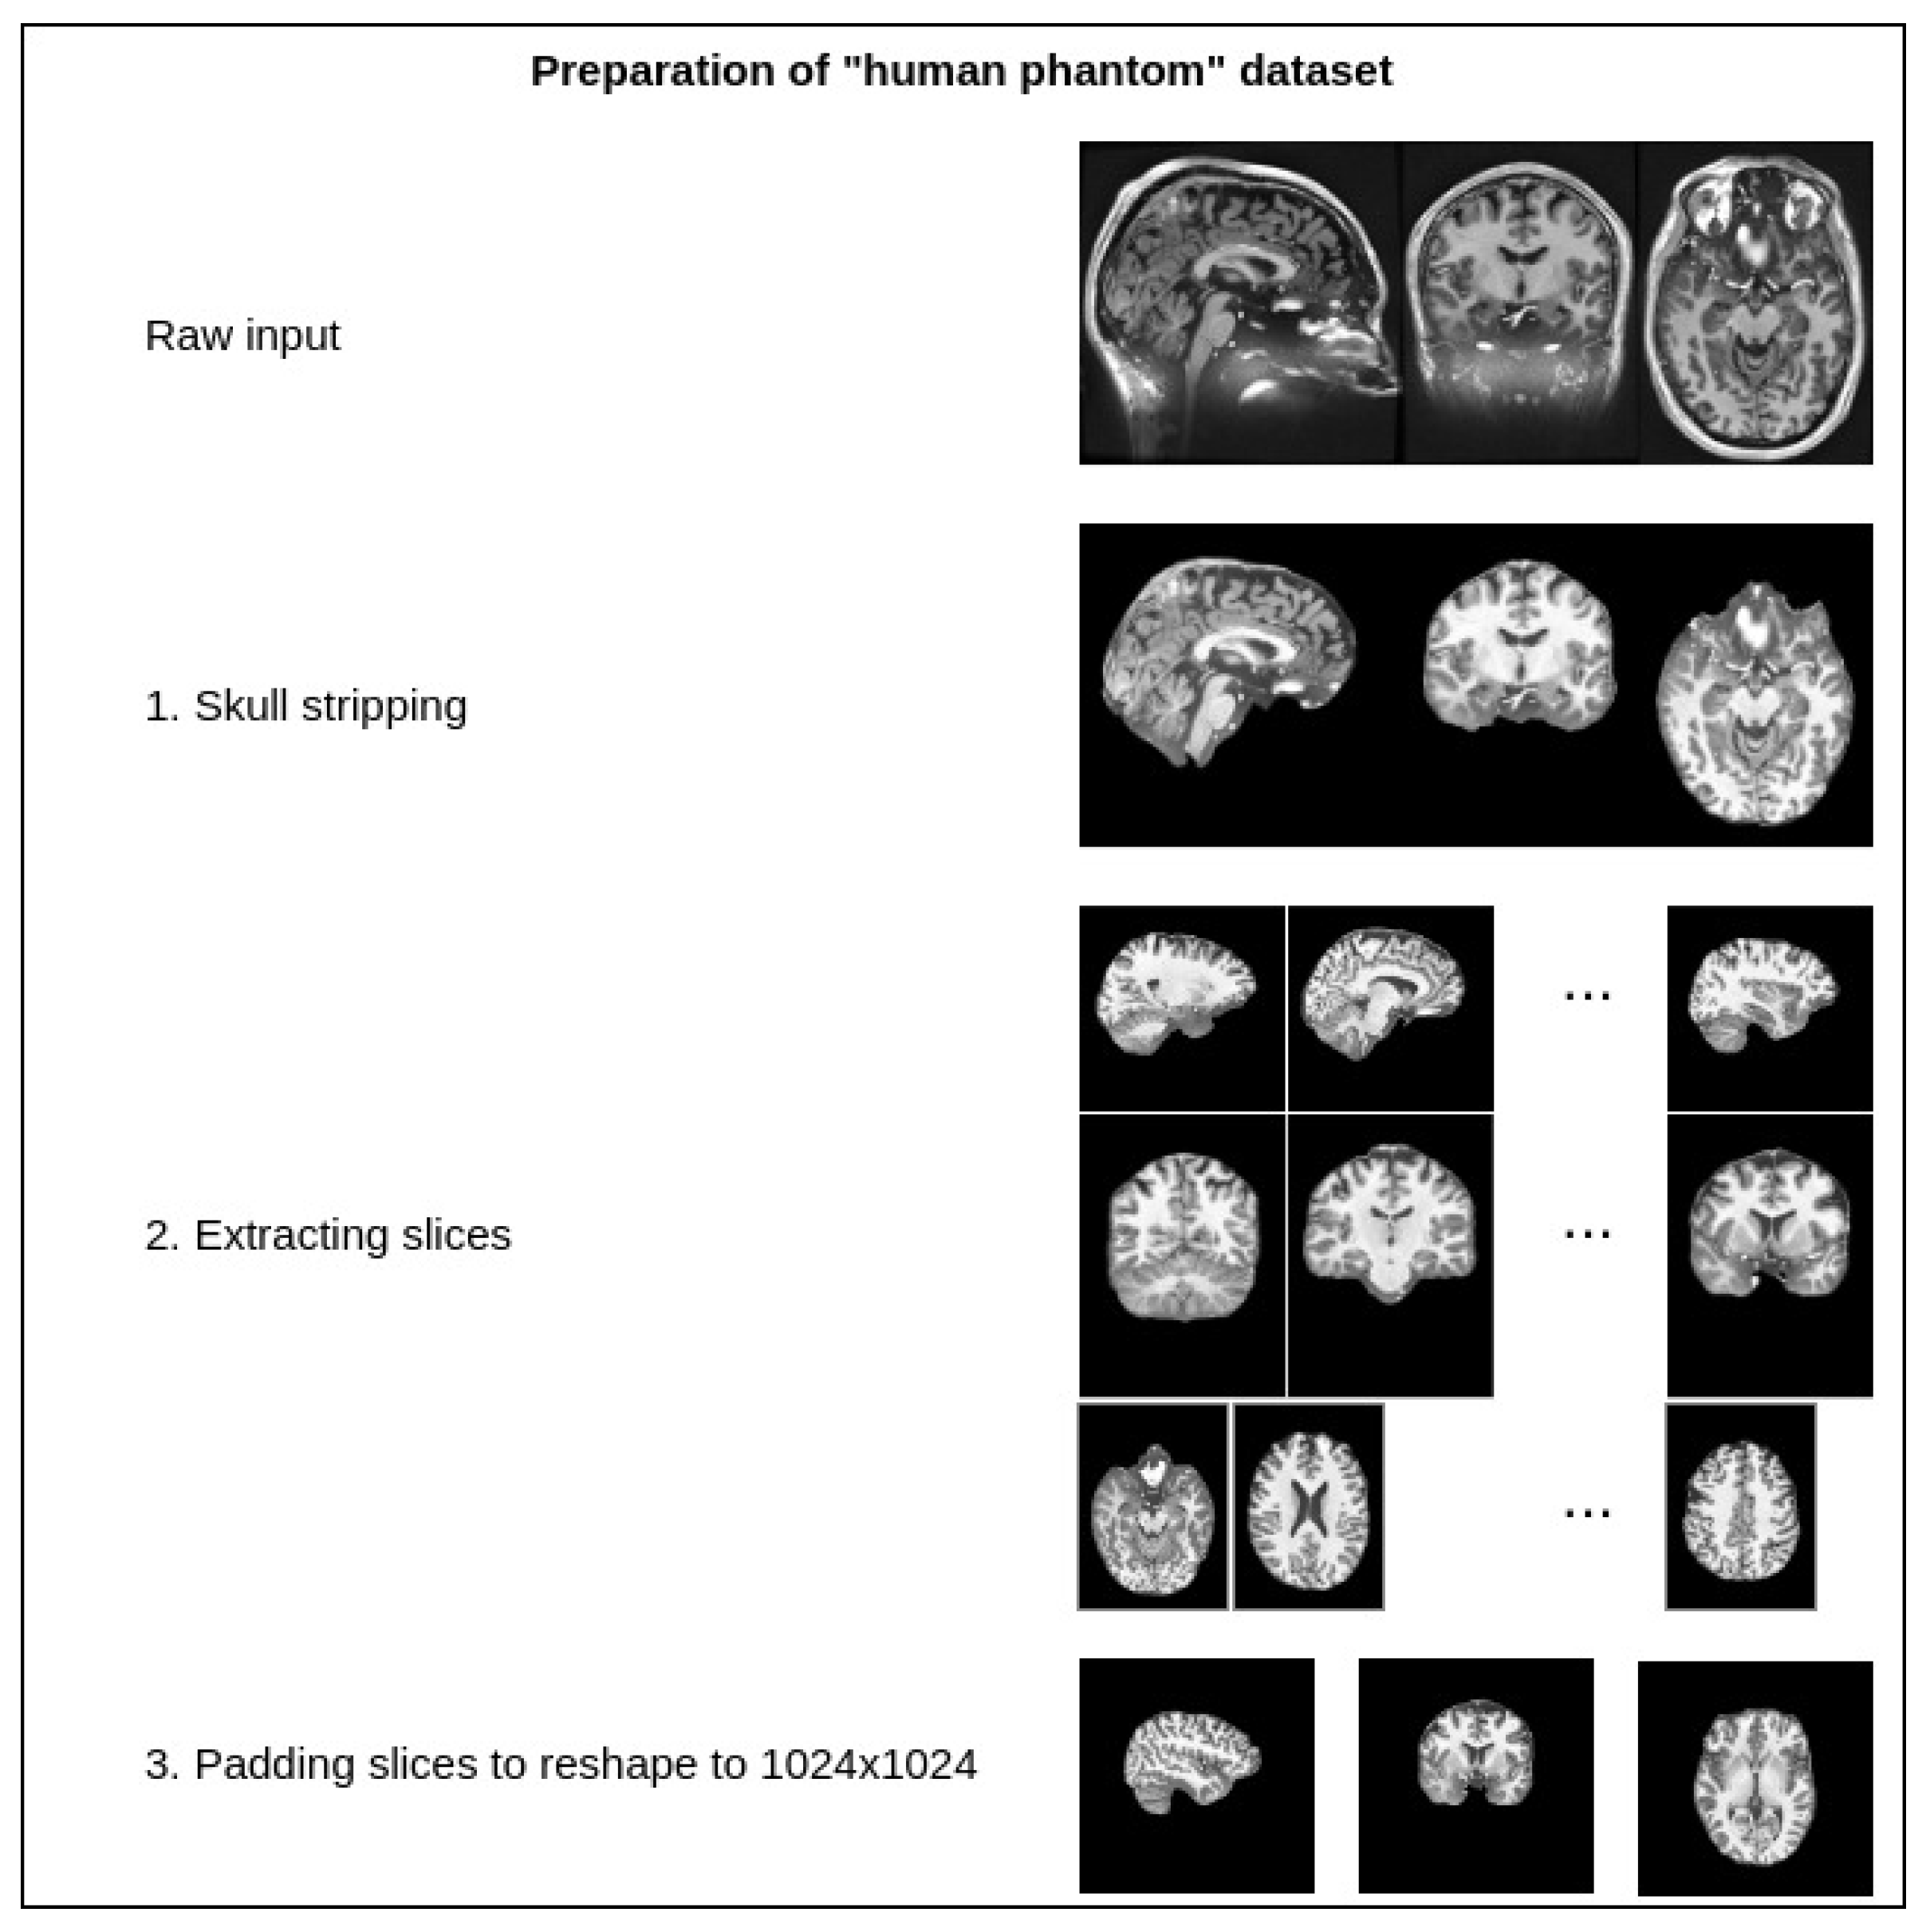

3. Materials and Methods

4.1. Experimentation Data